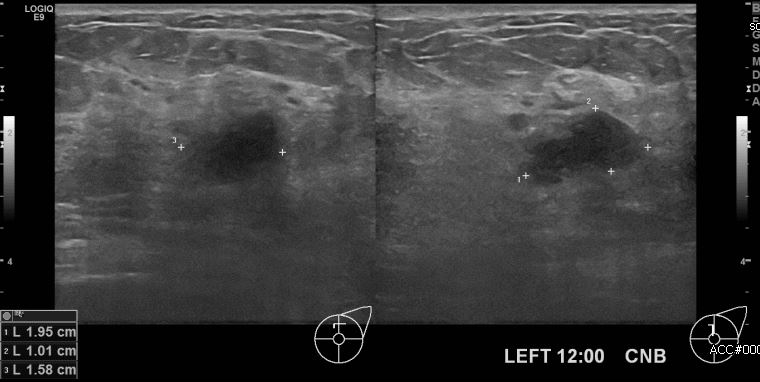

상기환자 건강검진상 이상소견으로 내원하신 50대 여성분으로  좌측 12시 방향

의심스러운 멍울 조직검사 시행하여 좌측 침윤성 유관암 진단되었습니다.